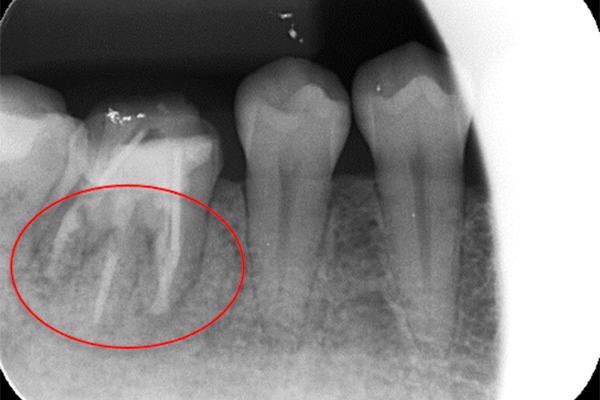

根の横に誤った穴をあけてしまい、気づかずに薬を入れてしまっている。また、器具が破折し、根の先に飛び出ている。

※本来の根管に薬が入ってることがわかります。